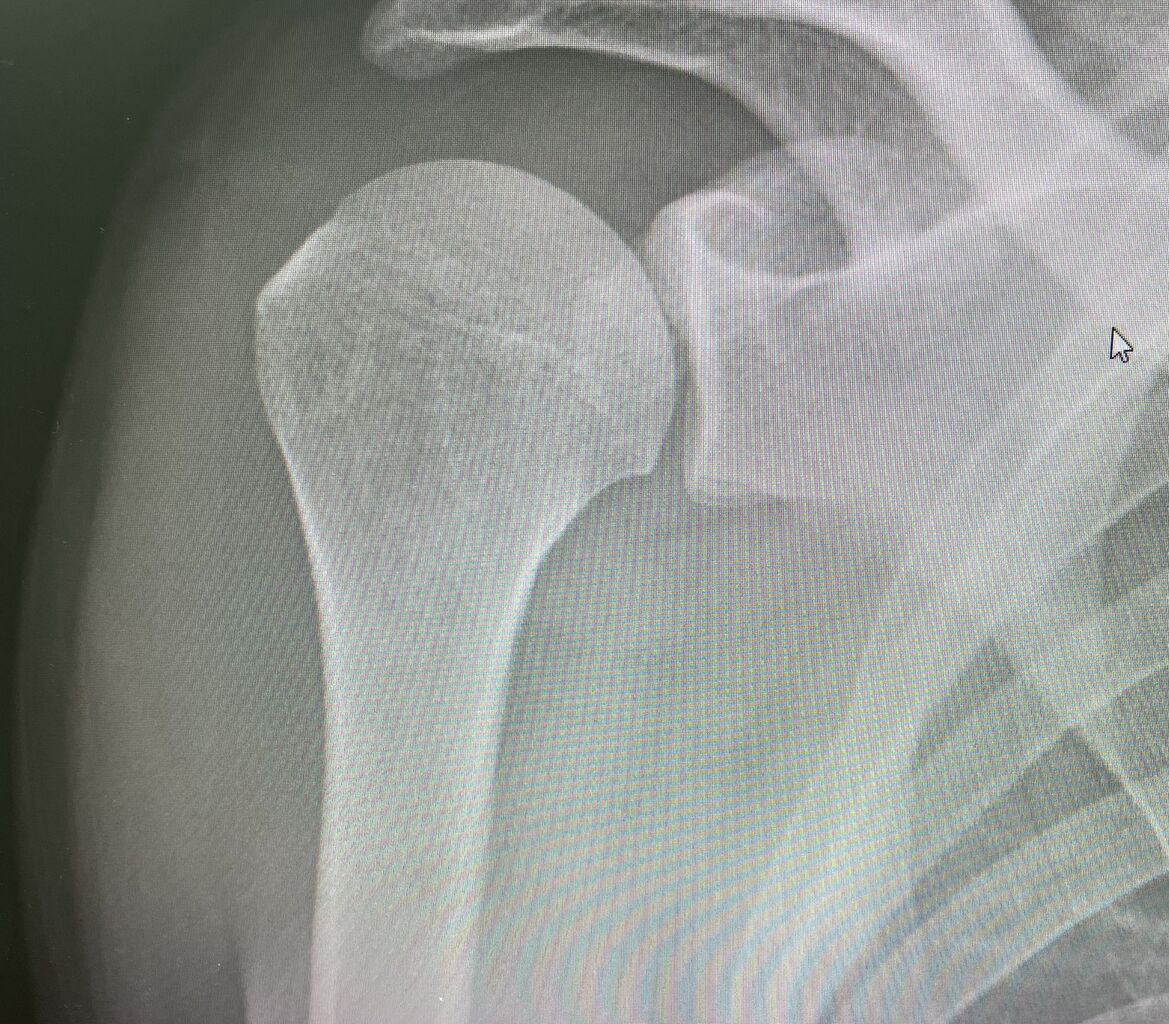

本日も、朝から夜まで、一般患者様を

見さしてもらいながら

トップアスリートが4人来ました

茨城トヨペット社会人野球、151キロを投げる

プロからスカウトをもらってる、ピッチャー、

IMG_8592

硬式社会人野球 147のキロを投げる、

元甲子園全国制覇をした、履正社高校の

エースピッチャー

IMG_8602

全日本高校空手道選手権優勝の  女子空手選手

IMG_8603

全日本モトクロス選手権、5回連続全日本

チャンピオンの

選手たちも来院されました!

IMG_8595

かなりハードでしたが、やりがいのある1日でした!